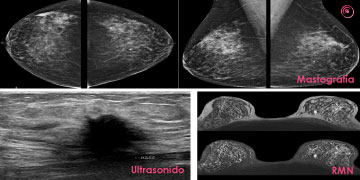

Los principales métodos de imagen utilizados para el área senológica o mastológica son: la Mastografía, el Ultrasonido (US) y la Resonancia Magnética Nuclear (RMN). En los últimos años se han agregado recursos tecnológicos para la mama como la Tomosíntesis (3D) , esta en investigaciones ha demostrado ser un excelente estudio para la detección temprana de cáncer de mama en tejidos glandulares densos gracias a su tecnología 3D, actualmente se valora que sea utilizado como screening mamario pero su elevado costo en algnos paises cuestiona este principio. También existe la Tomografía por Emisión de Positrones (PET) pero algunos de los métodos de imagen pueden ser indicados para casos específicos en los que se necesite precisar aún más el diagnóstico imagenológico o en aquellos casos que los estudios principales reflejen alguna duda o vacíos.

Existe un principio que se debe recordar y es que no existe un método de imagen único, perfecto o infalible para la mama, los estudios imagenológicos mamarios se complementan uno con otro para obtener los mejores resultados diagnósticos, esto se evidencia con el hecho de que existen imágenes que no son visibles con la mastografía, así como otras lesiones mamarias como las microcalcificaciones que no se observan mediante ultrasonido, es por eso, que lo ideal es realizar ambos estudios y así las probabilidades de detección de lesiones no palpables o muy pequeñas es altísima.